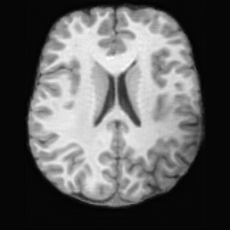

Healthy w/Lesion MaskPathologicalDifferencew/o LCGw/ LCG(a)Refer to captionRefer to captionRefer to captionRefer to captionRefer to captionRefer to captionHealthy w/Lesion MaskPathologicalDifferencew/o LCGw/ LCG(b)Refer to captionRefer to captionRefer to captionRefer to captionRefer to captionRefer to caption

Figure 7: Ablation study of Lesion Consistency Guidance (LCG). Without LCG, the generated pathological regions are indistinct and show weak pathological expression in both examples.

Lesion Consistency Guidance. Fig. 7 illustrates the impact of Lesion Consistency Guidance (LCG) for healthy-to-pathology editing. Without LCG, the generated lesion regions appear blurry around lesion boundaries, and the pathological patterns are less distinct, resulting in ambiguous lesion localization and weak pathological expression. Incorporating LCG produces lesions with more precise localization and well-defined shapes that better align with the given lesion masks, as well as textures and contrasts that exhibit stronger pathological characteristics. These results demonstrate that LCG effectively enforces lesion-aware conditioning, enhancing both spatial and semantic consistency of the generated pathological regions.